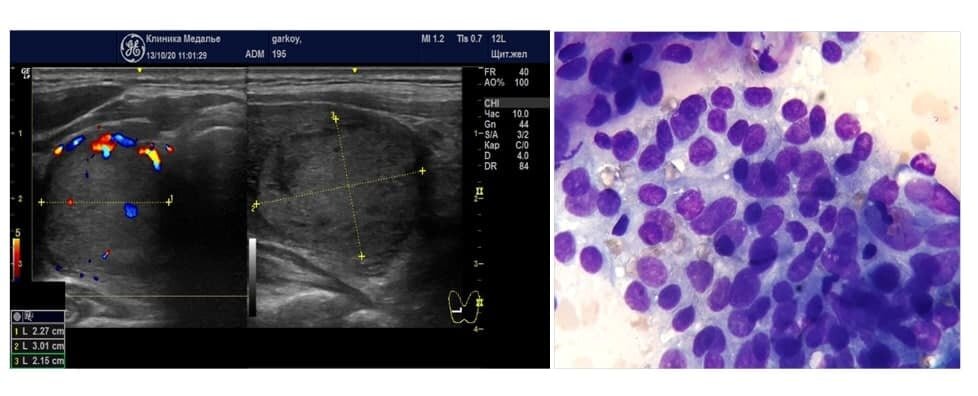

На второй фотографии – это средняя ситуация - видны и клетки с признаками секреторной активности, и клетки маленькие, неактивные, кровоток в узле умеренный. Это рабочий узел, средней степени активности.